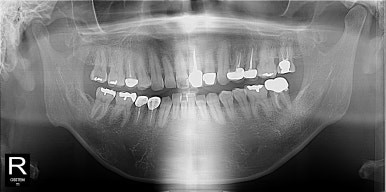

1년만에 다시 오신 겁 많은 환자분

1년전 4월 치과가 너무 무섭다고 수면마취로 충치치료를 받고는 발치 치료를 미루시다가 다시 오신 환자분, 수면마취 첫 블로그 글의 주인공~

오른쪽 위 어금니 충치가 심해서 발치를 하자고 했었는데 미루시다가 이제는 너무 불편해서 안되겠다고 당분간 일을 쉬게 되어서 여유있게 다른 치료도 받고싶다고 하셨다.

원래 발치하기로 했던 치아는 더 썩어서 부러져 있어고 좌측 아래 작은 어금니도 그동안 충치가 많이 진행되어 신경치료가 필요한 상황이었다.